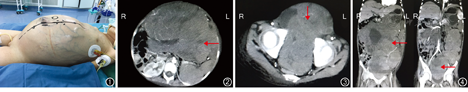

患儿女,6岁,回族。因左肾母细胞瘤术后7个月,腹部胀痛1个月于2016年12月24日收入我院。患儿于2016年5月在当地医院行左肾母细胞瘤根治术,术后因经济原因,未接受化疗。2016年11月患儿出现腹部胀痛不适,逐渐加重,腹部逐渐膨隆。既往无其他特殊病史。体格检查:心率140次/min、呼吸30次/min、血压90/70 mmHg(1 mmHg=0.133 kPa)、身高110 cm、体质量21 kg。根据文献[1]的标准,患儿营养风险评分为4分。强迫坐位、侧卧位,不能平卧。咳嗽,咳白色泡沫痰。双肺呼吸音粗。心音有力,心律齐。腹部膨隆,腹壁静脉广泛曲张(图1)。左季肋区可见斜行切口瘢痕。全腹软,腹部肿瘤质地坚硬,表面光滑,边界不明确,有压痛。

入院检查:血常规检查:Hb 86 g/L、PLT 354×109/L、WBC 9.25×109/L。肝功能检查:ALT 24 U/L、AST 54 U/L、Alb 26.5 g/L、TBil 6.71 μmol/L。电解质、凝血功能、肾功能正常。心电图:窦性心动过速。心脏彩色多普勒超声检查:房间隔中部可见左向右分流束,考虑房间隔缺损。双下肢静脉通畅,无血栓。腹部彩色多普勒超声检查:腹腔囊实性混合性包块,大小约31 cm×24 cm×13 cm。CT检查:肺间质水肿渗出,两肺下叶膨胀不良。腹腔、左侧腹膜后及盆腔巨大包块,大小约30 cm×20 cm×14 cm,腹膜后淋巴结增大(图2,图3,图4)。初步诊断:腹、盆腔恶性肿瘤;左肾母细胞瘤切除术后、营养不良、中度贫血、低蛋白血症、房间隔缺损。

放射科医师:腹腔包块考虑肿瘤复发并种植转移,瘤内大量瘤血管,轻中度强化,肠管及腹部大血管大多受压向右侧移位,无明显侵犯,胰腺及脾脏受压移位。右肾代偿性增大。